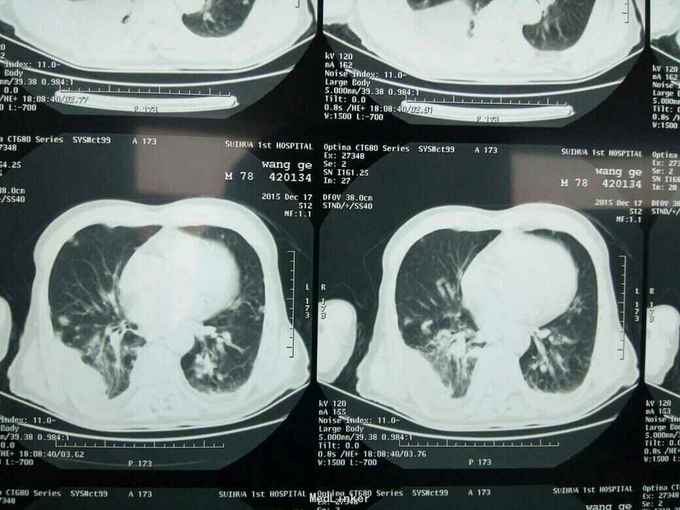

根据病史查体诊断:腰间盘突出症待确诊。应用消肿营养神经镇痛治疗。一天。查核磁共振示:腰椎多节段间盘突出伴椎管狭窄。第二腰椎骨破坏侵及椎板。部分突入椎管,脊髓受压。诊断:腰间盘突出伴椎管狭窄。第二腰椎转移癌,脊髓受压。经与家属沟通,查双肺CT:双肺下叶炎症。肺部纤维化。可见肿瘤阴影。肋骨及胸膜受累。胸椎部分骨破坏。最终诊断:双肺癌,胸椎,腰椎骨转移,脊髓受压。多节段腰椎间盘突出。病人至肿瘤科治疗。